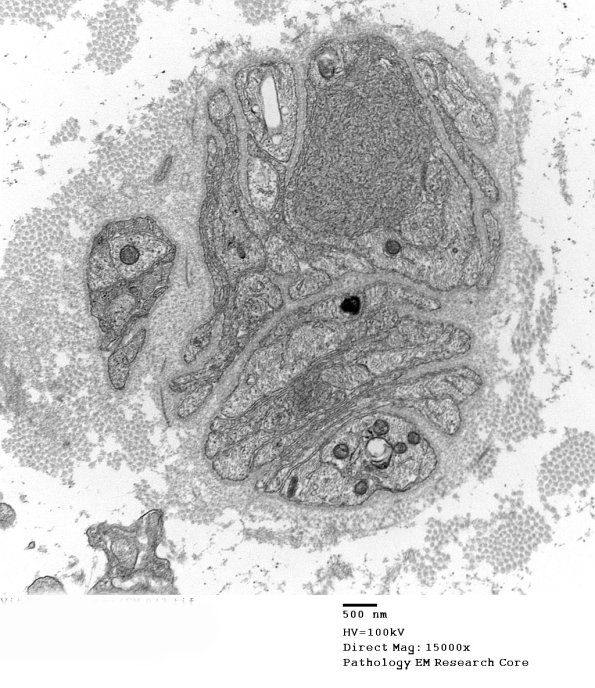

11Q1,2 The axoplasm intervening between anastomosing elements appears denser than expected, true of many dystrophic axons. (electron micrographs)